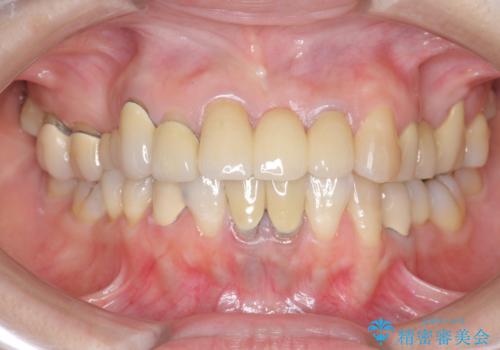

前歯ブリッジのやりかえ

- 前歯の審美障害、見た目の改善を希望され来院されました。

歯肉縁下カリエスも認められるため、挺出を行いセラミックブリッジを審美的に新製します。